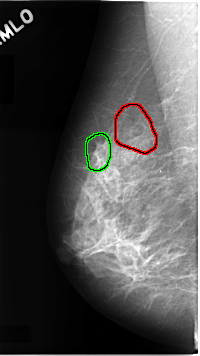

FILE: C_0068_1.RIGHT_MLO.OVERLAY

TOTAL_ABNORMALITIES 2

ABNORMALITY 1

LESION_TYPE CALCIFICATION TYPE AMORPHOUS DISTRIBUTION SEGMENTAL

ASSESSMENT 5

SUBTLETY 3

PATHOLOGY MALIGNANT

TOTAL_OUTLINES 1

BOUNDARY

ABNORMALITY 2

LESION_TYPE MASS SHAPE ARCHITECTURAL_DISTORTION MARGINS SPICULATED